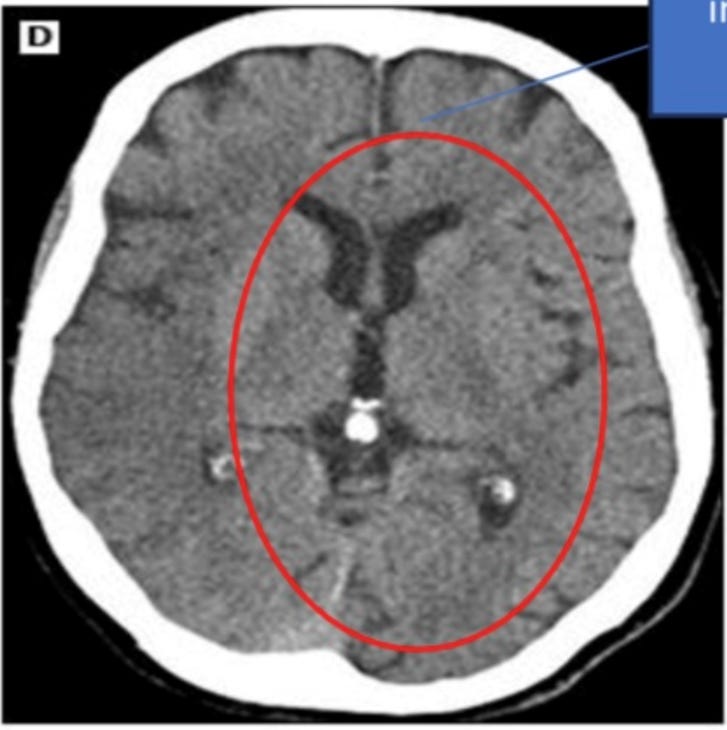

Voici une dans le cerveau :

L'examen TEP cérébral haute définition montre la micropuce au même endroit :